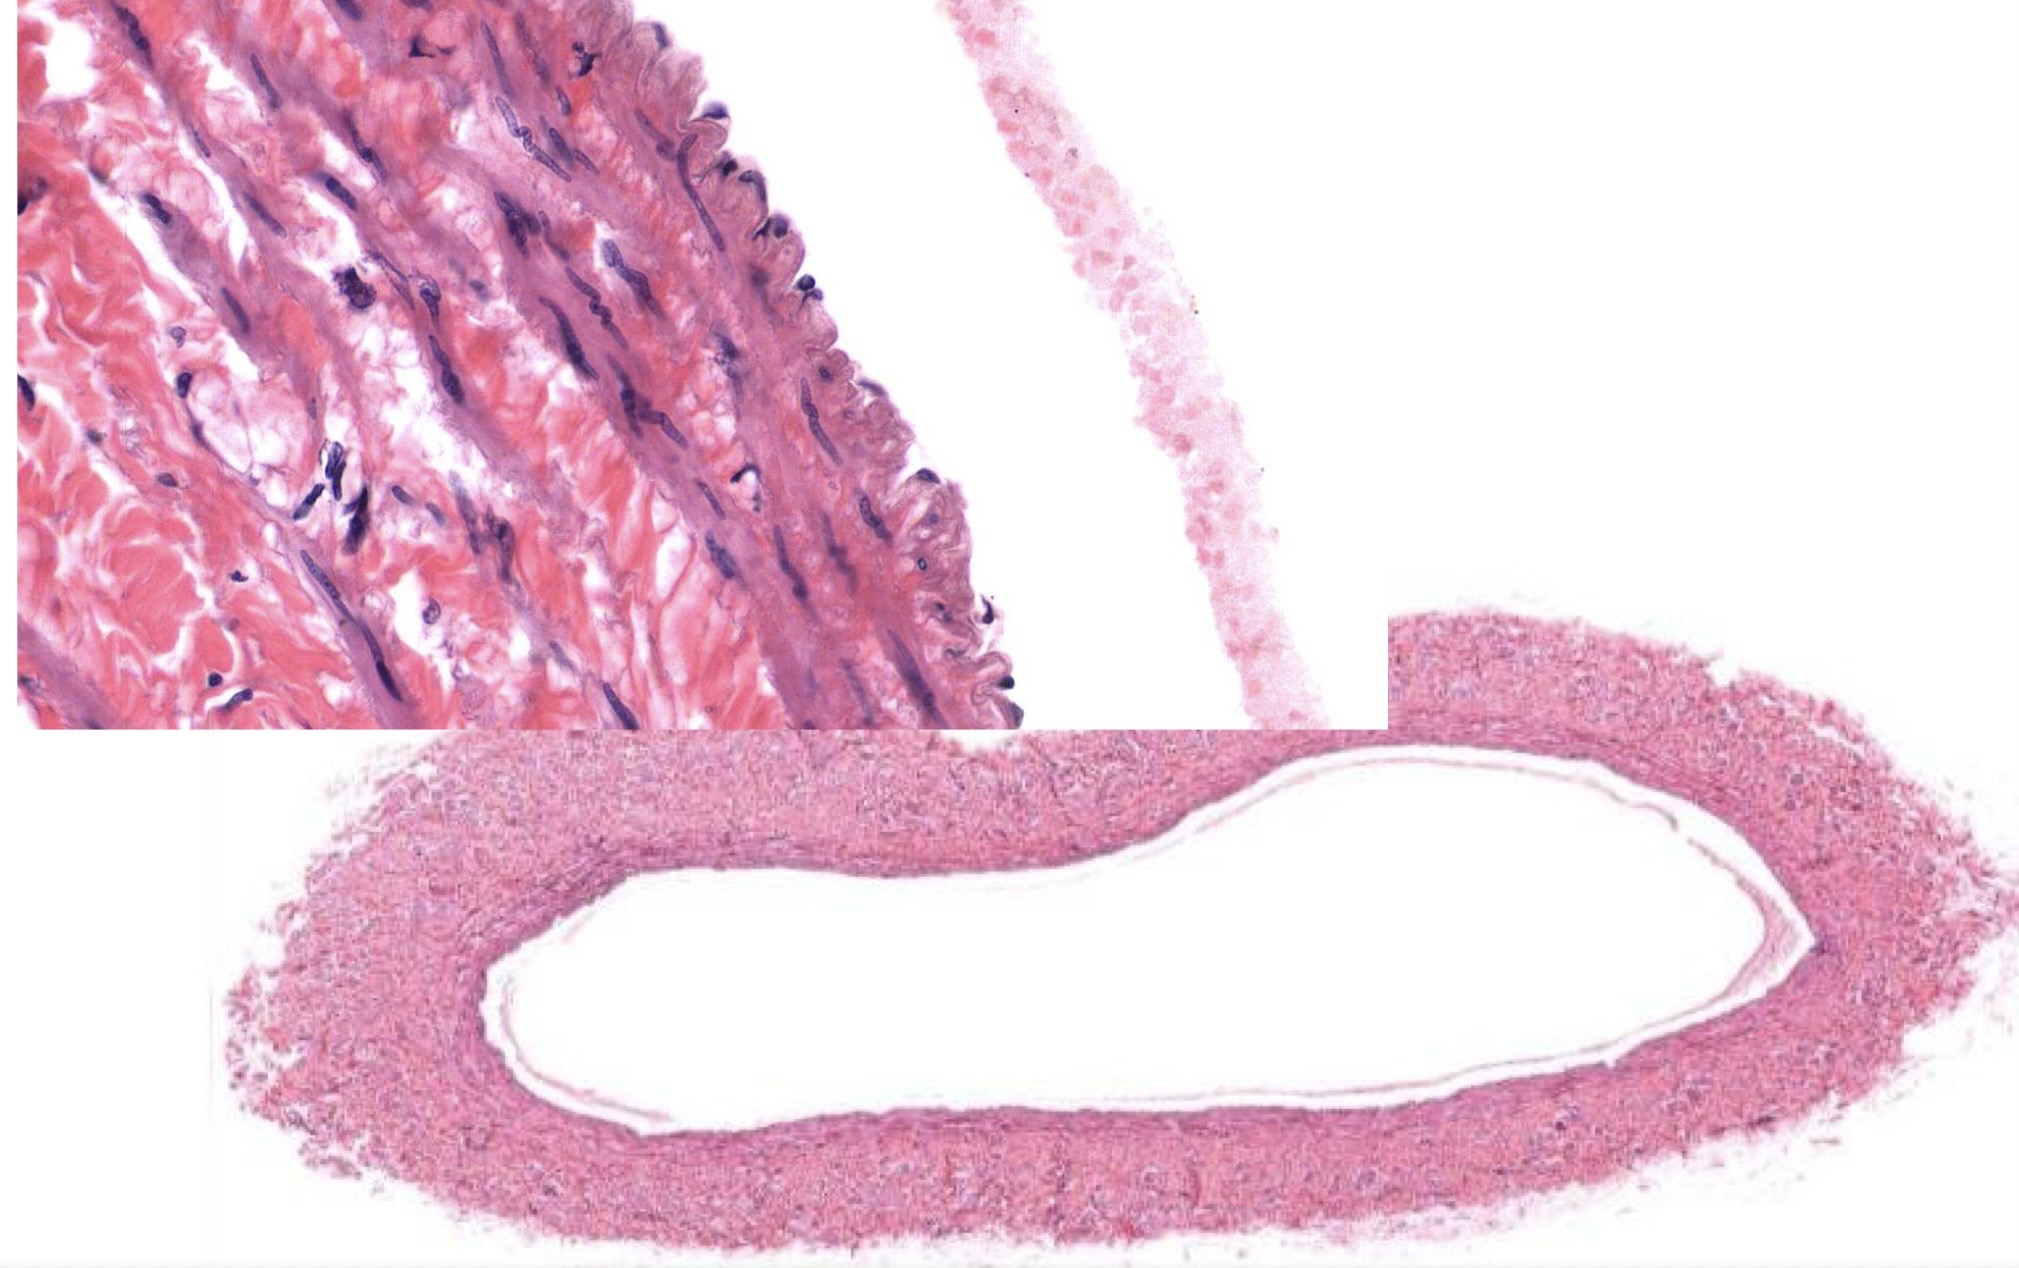

Idenitfy the Vessel and what are the Properties?

Large Vein

returns blood to heart

Ti made of endot

Tm made of some elastic F + 5 layers of Smooth M

Te made of DICT bundles/swirls! w/ vasa vasorum

Identify the Vessel and the Layer pictured

Large Vein Ti

Large Vein Tm

Large Vein Ta!